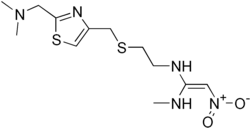

В 1975-м году появился циметидин («Smith Kline and French»), в 1979-м — ранитидин («Smith Kline and French»), в 1984-м — фамотидин («Merck»), в 1987-м — низатидин («Eli Lilly and Company», США). H2-блокаторы сразу стали «золотым стандартом» терапии кислотозависимых заболеваний, а ранитидин к 1988 году — наиболее продаваемым рецептурным препаратом и оставались ими до появления ингибиторов протонного насоса (омепразола).

H2-блокаторы IV и V поколений низатидин и роксатидин на практике мало чем отличаются от фамотидина и не имеют перед ним существенных преимуществ, а роксатидин даже немного проигрывает фамотидину в кислотоподавляющей активности[4].